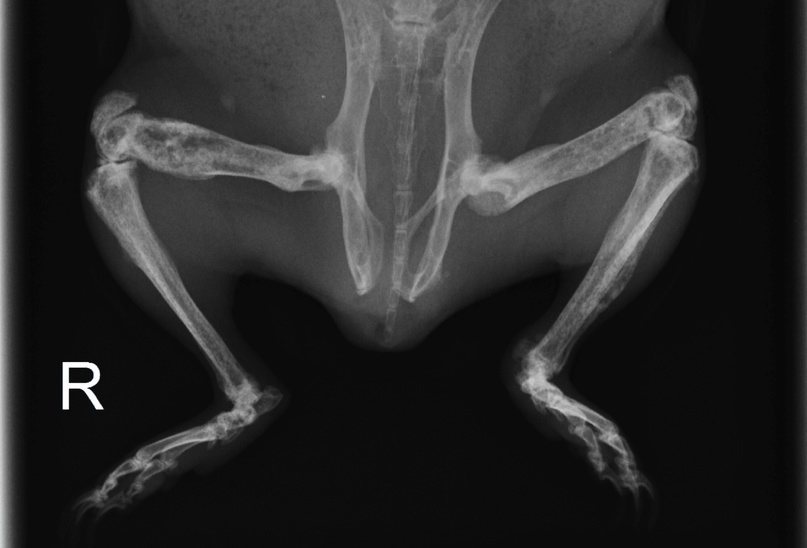

- Рентгеновские снимки для точной оценки скелета

Диагноз обычно ставится посредством сочетания клинического обследования и рентгенографии, которые выявляют изменения в костях. Анализы крови также могут быть полезны для проверки уровня кальция в крови и исключения других заболеваний.